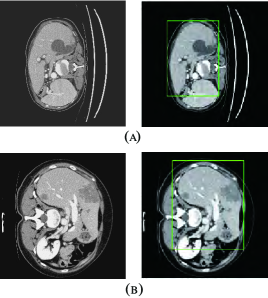

Refer to caption

Figure 7: Liver localization using RA-UNet-\@slowromancapi@. From left to right the figure shows the preprocessed slice, and the final boundary box which restricts the liver region. (a) A typical slice from the LiTS validation dataset. (b) A typical slice from the 3DIRCADb dataset. The RA-UNet-\@slowromancapi@ enables the coarse localization of liver regions.

After stacking all the slices and employing the 3D connect-component labeling, we calculated the 3D boundary box of the slices with liver, and extended 10 pixels in coronal, sagittal, and axial directions to ensure that the entire liver region was included. Fig. 7 shows the liver localization results from RA-UNet-\@slowromancapi@. It demonstrates that the attention mechanism has successfully constrained the liver region, and RA-UNet-\@slowromancapi@ can greatly restrict the liver region within a boundary box.